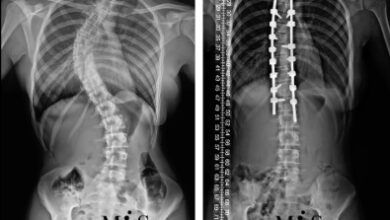

• الجنف (Scoliosis)

قال تعالى: (وَإِذۡ تَأَذَّنَ رَبُّكُمۡ لَئِن شَكَرۡتُمۡ لَأَزِيدَنَّكُمۡۖ وَلَئِن كَفَرۡتُمۡ إِنَّ عَذَابِي لَشَدِيدٞ ) ما هو الجنف (Scoliosis)؟ الجنف هو انحناء غير طبيعي…